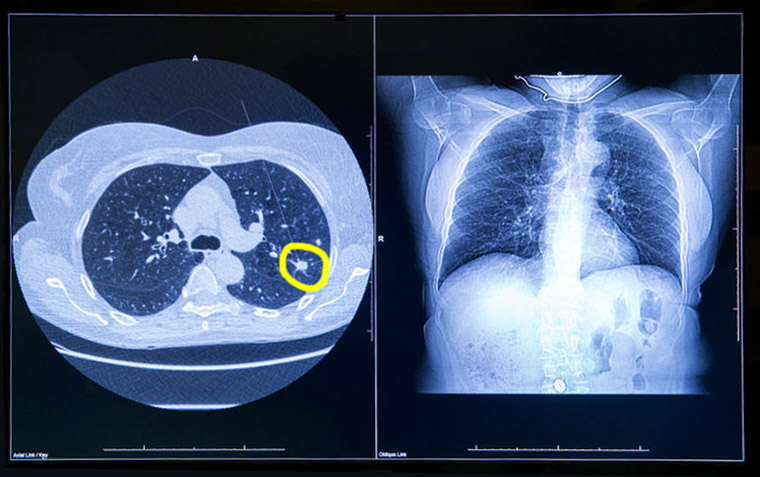

Sobrediagnóstico en el rastreo de cáncer de pulmón

14 agosto 2018

En el estudio danés de tomografía computada de baja dosis para el cribado de cáncer de pulmón se halló que 2 de cada 3 casos detectados podrían corrresponder a sobrediagnóstico. JAMA Internal Medicine, 13 de agosto de 2018